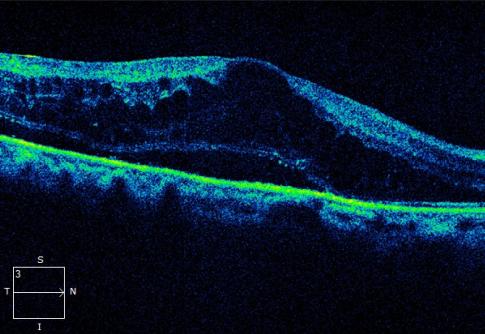

光学相干断层扫描(OCT) :可精确测量黄斑区的厚度和水肿程度

黄斑水肿 OCT表现